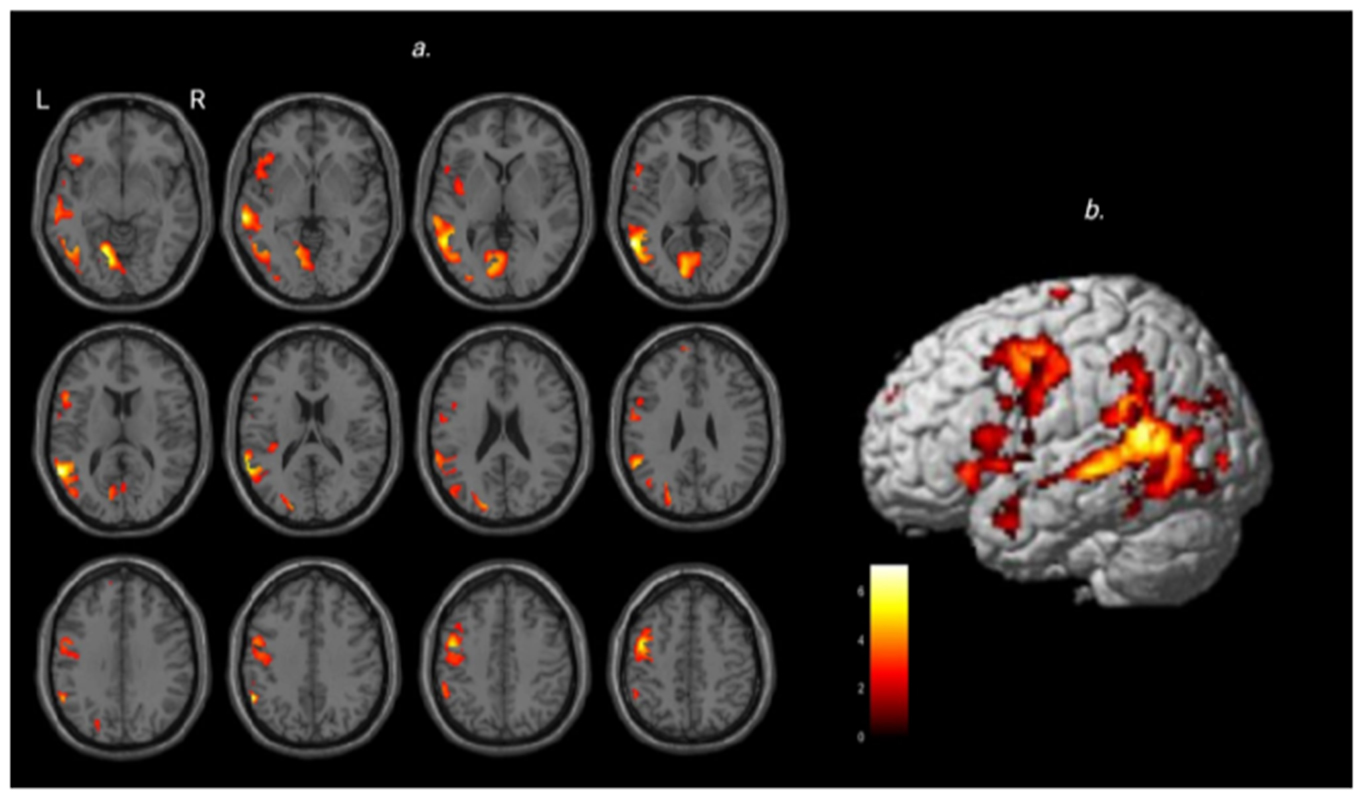

Mediante la utilización de técnicas de neuroimagen y un paradigma experimental novedoso, identificaron regiones cerebrales que trabajan en conjunto durante la comprensión del sarcasmo. A partir de combinar texto e imagen, o presentar sólo la imagen o sólo el texto, se propusieron delimitar cómo se activan diferencialmente áreas neuronales al interpretar el mismo enunciado (“¡Qué bien se viaja!”) con dos intencionalidades enunciativas: sarcástica y literal.

Las áreas del cerebro implicadas

Según la investigación, las áreas del cerebro implicadas incluyen: la corteza prefrontal medial, clave para entender las intenciones del otro, la unión temporoparietal, especializada en representar estados mentales ajenos; la ínsula izquierda y la amígdala, implicadas en evaluar emociones y empatía, y áreas del lenguaje como la corteza temporal superior y la circunvolución frontal inferior, necesarias para interpretar el significado en contexto. También permiten explorar nuevas vías para detectar y tratar condiciones neurológicas. “Las áreas del sarcasmo o del lenguaje figurativo son accesorias. Las utilizamos cotidianamente, pero ante una lesión neurológica podrían reclutarse para compensar funciones dañadas –expresa Bendersky–. En enfermedades como epilepsia o trastorno del espectro autista, esta capacidad de entender el sarcasmo se puede perder”.